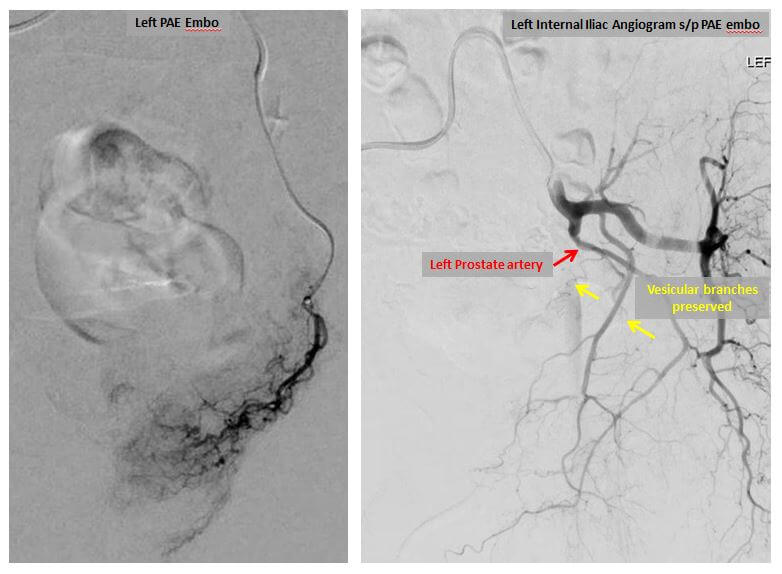

Once the prostatic arteries have been identified, the catheter is repositioned under X-ray guidance and moved into the left prostatic artery. X-ray dye is again injected in order to confirm the position of the catheter. Once this is done, small particles or microspheres are injected into the catheter in order to stop the flow of blood within the left prostatic artery. Once it is injected, the microspheres induce inflammation, slow blood flow, and create clot formation within the artery. When blood flow has stopped within the left prostatic artery, the catheter is repositioned into the right prostatic artery and the procedure is repeated. In our experience, most patients can be embolized with a single catheter entering the arterial system on the right side; a second catheter placed into the left common femoral artery is necessary only in the most difficult cases. Once the embolization is complete, the catheter is removed and a seal is placed into the right common femoral artery to insure that there will be no bleeding from the site. The length of the procedure is variable and highly dependent upon the complexity of the arterial anatomy.

Left prostatic artery angiograms before (left image) and after embolization (right image).